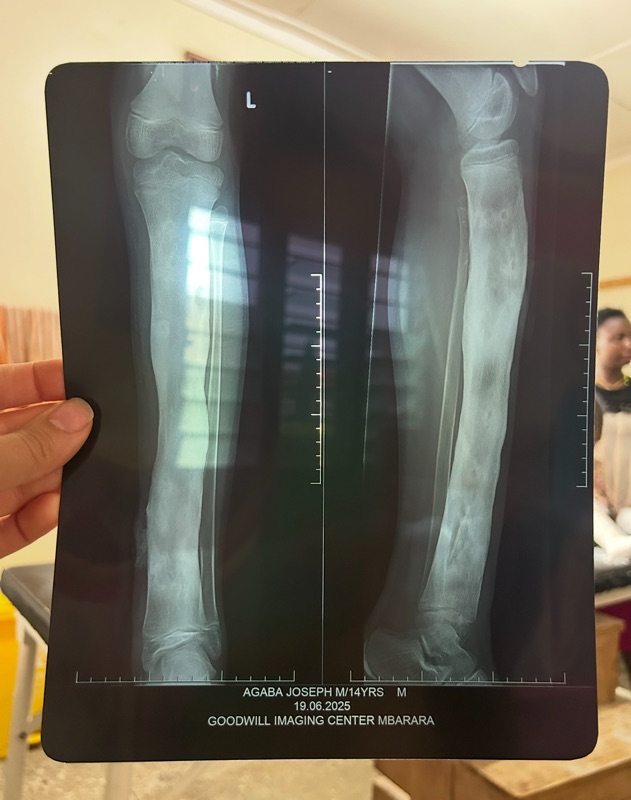

- Este mes se han realizado 4 operaciones una de ellas para retirar un tumor cancerígeno a Cecilia. También han sido operados Joseph, Darius y Lydia. El precio de las 4 operaciones ha sido de 431€.